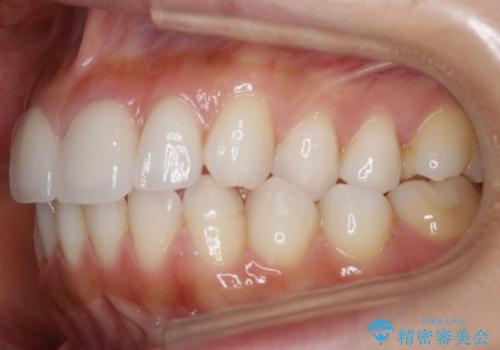

【非抜歯】噛み合わせを整えたい! インビザライン矯正

- 嚙み合わせのズレを主訴にご来院されました。

前歯・奥歯ともにセラミッククラウンで治療されている歯があったため、その歯にあまり影響が出ない範囲内で全体の噛み合わせが良くなるような動きを組み込んで治療を進めることとなりました。